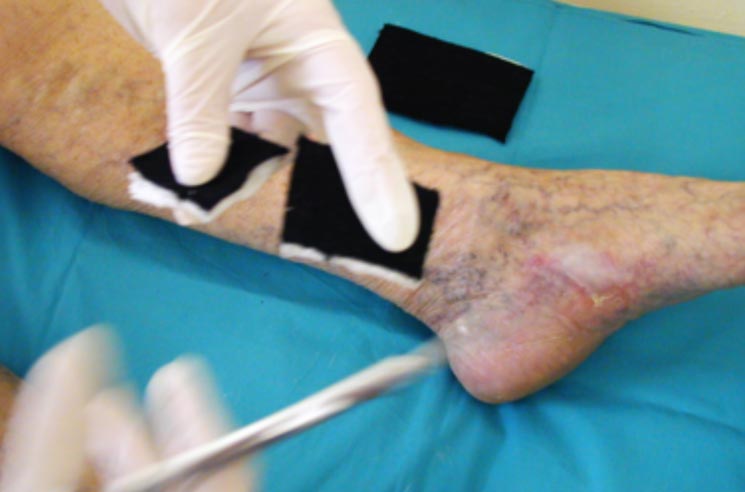

Zahájení léčby a stav po 22 převazech

Zahájení léčby a stav po 22 převazech.